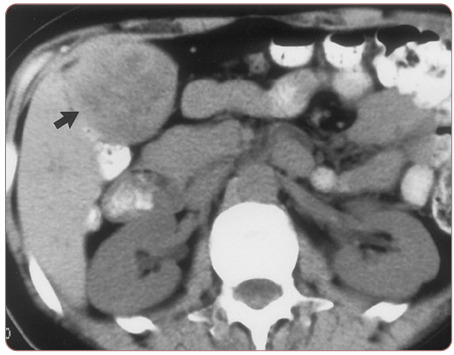

Aplastic anemia (AA) is a bone marrow failure disorder resulting in peripheral pancytopenia and marrow hypoplasia. An alternative diagnosis of hypoplastic myelodysplastic syndrome (MDS) can overlap this diagnosis but is differentiated by the presence of dysplastic progenitor cells. Since AA can be characterized as an autoimmune disease directed against hematopoietic stem cells, its presence can potentially increase susceptibility to alternate malignancies. Hypoplastic MDS, however, can present itself in an extramedullary fashion solely or as a relapse of acute myeloid leukemia resulting in symptoms similar to those described in this case study. Solid tumor malignancies may also result in abnormal blood counts, creating a wide differential diagnosis. This manuscript presents a case of untreated AA in a patient presenting later with severe abdominal bloating.